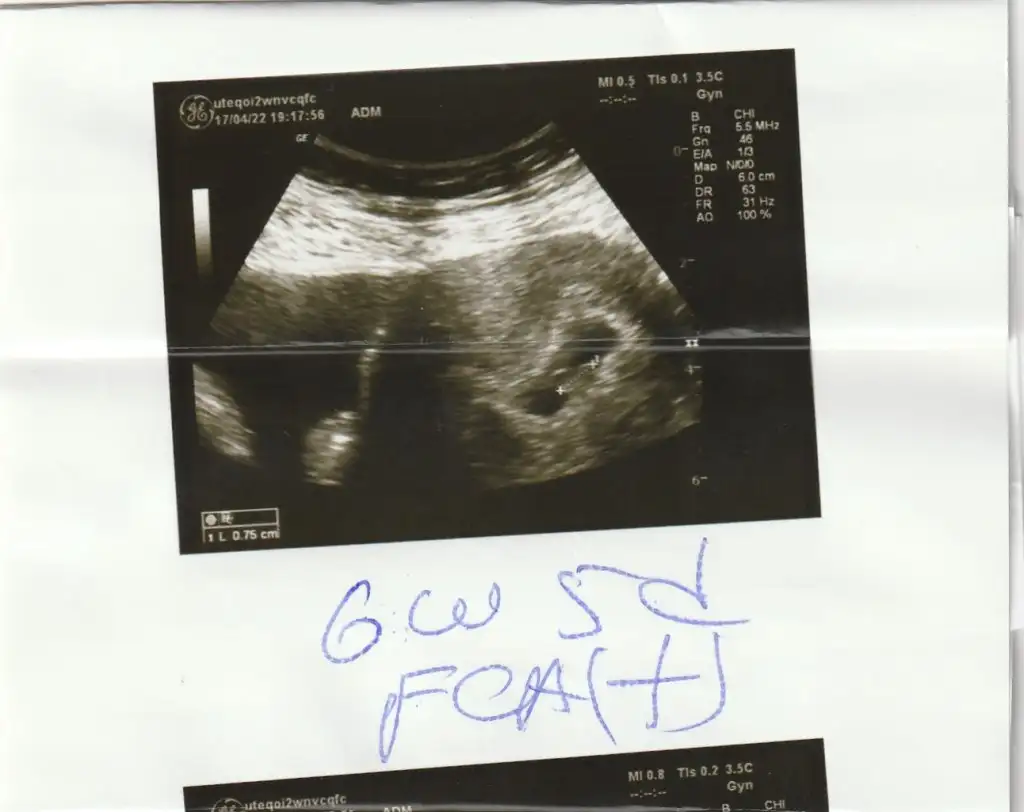

karından mı canımMerhaba bana da yorum yapar mısınız?6+2 haftalıkEki Görüntüle 3051268

Merhaba bana da yorum yapar mısınız?6+2 haftalıkEki Görüntüle 3051268

Prenses canımMerhaba bana da yorum yapar mısınız?6+2 haftalıkEki Görüntüle 3051268